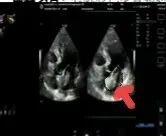

術(shù)后超聲

術(shù)后病理顯示,患者左房腫瘤為良性黏液瘤,完整切除后無(wú)需后續(xù)治療。經(jīng)過(guò)10天的康復(fù)治療,老人順利出院。這一案例中,多學(xué)科團(tuán)隊(duì)通過(guò)術(shù)前風(fēng)險(xiǎn)分層、術(shù)中精密協(xié)作、術(shù)后個(gè)體化護(hù)理,為高齡復(fù)雜心臟疾病患者的救治積累了臨床經(jīng)驗(yàn)